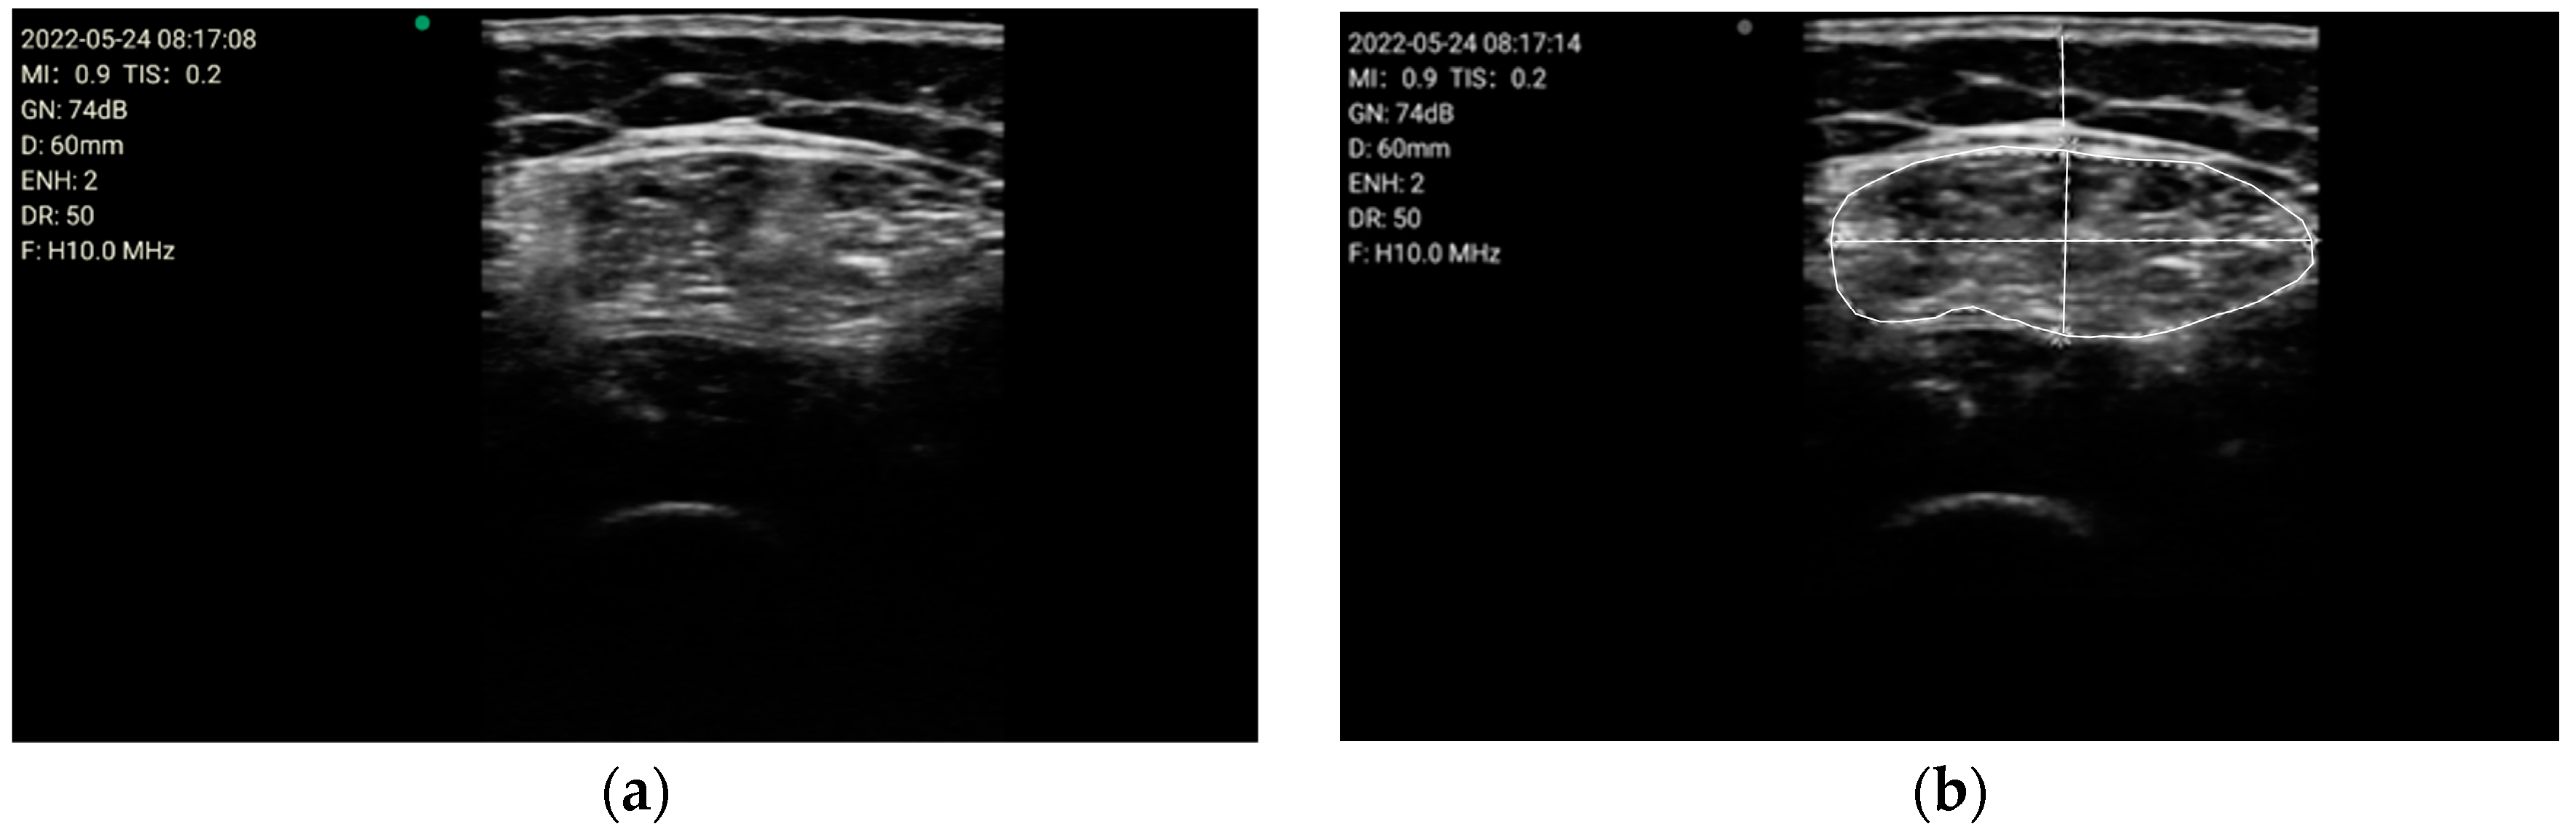

- Compare the measurements of the unilateral (right) RF of the patients performed by the expert evaluator (rater 1) using the standard tools included in the ultrasound image device (i.e., method A), see Figure 2, with those obtained by applying the PIIXMEDTM Ultrasound Imaging System (Dawako Medtech S.L., Valencia, Spain) (rater 2) (i.e., method B) [15,16,17,18,19] on the same acquired raw images, see Figure 3 and Figure 4.

Figure 2. (a) Acquired raw ultrasound image of the unilateral (right) quadriceps rectus femoris muscle in the transverse plane measure by rater 1 (i.e., method A); (b) Measurement of the variables by the conventional method using the ultrasound imaging device tools, by rater 1 (i.e., method A), for the parameters of the cross-sectional area, the Y-axis, i.e., transverse muscle thickness (MT), and the subcutaneous fat thickness (SFT).